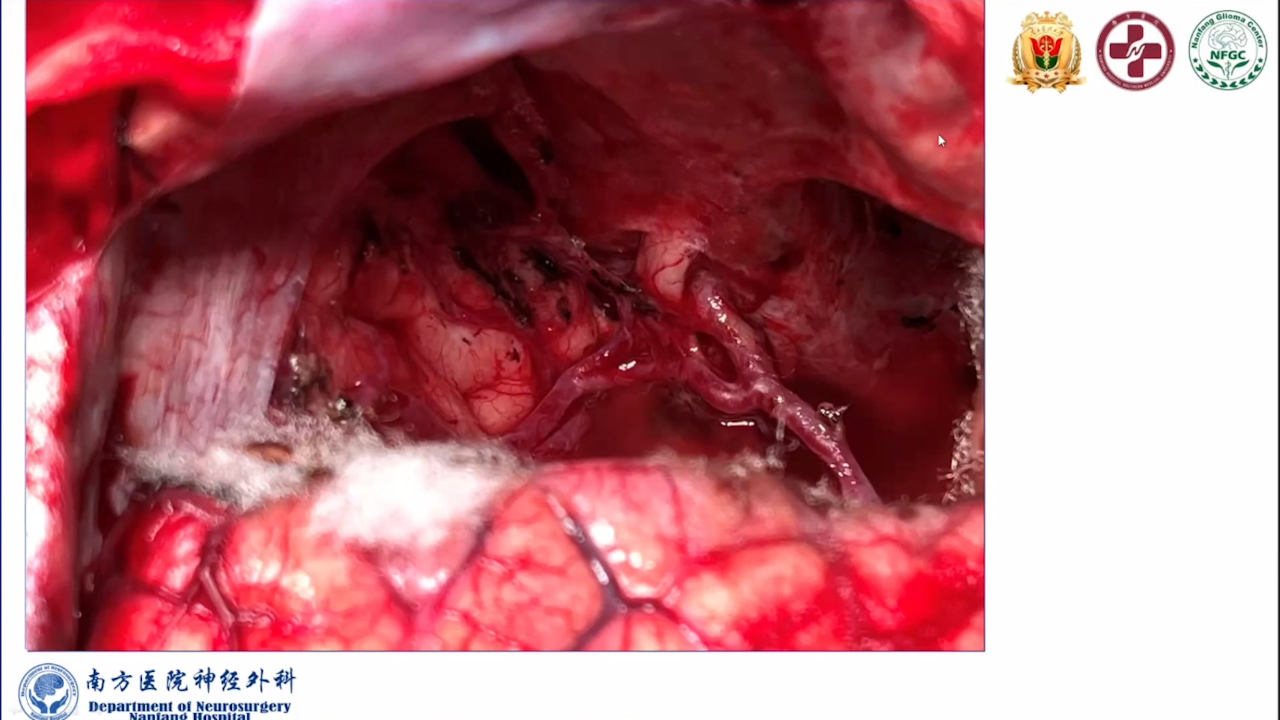

巨大的脑胶质瘤往往破坏皮层功能,推挤白质纤维束,包裹重要供血动脉,正常解剖结构移位。手术切除病变可以挽救患者生命。如果术中确保重要动脉不损伤,并在术前纤维束成像指导下按照解剖结构标志尽可能保留神经纤维束,患者将在获得辅助治疗机会的同时,神经功能也得以逐步恢复,更有利于脑胶质瘤的预后。